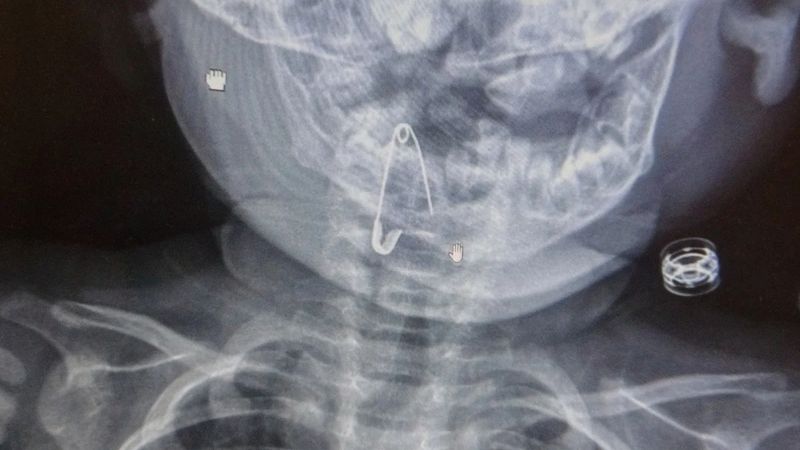

Öksürmeye başlayan minik çocuğun, hastanede çekilen röntgen sonucu çengelli iğneyi yuttuğu fark edildi.

Çengelli iğnenin saplı olduğu soluk borusundan çıkarılan bebek, 2 saatlik gözlemin ardından taburcu edildi.

“8 aylık bir bebek, Bitlis’in Güroymak ilçesinden tarafımıza danışıldı. Güroymak ilçesinde çekilen röntgen sonucunda çengelli iğnenin soluk borusunun girişinde olduğunu teyit ettik. Yapılan müdahaleler sonucunda çengelli iğneyi çıkardık. Çıkardıktan sonra iki saat kadar gözlem altında tuttuk hastamızı. Daha sonrasında herhangi bir komplikasyonla karşılaşmadık ve sorunsuz bir şekilde taburcu ettik.”